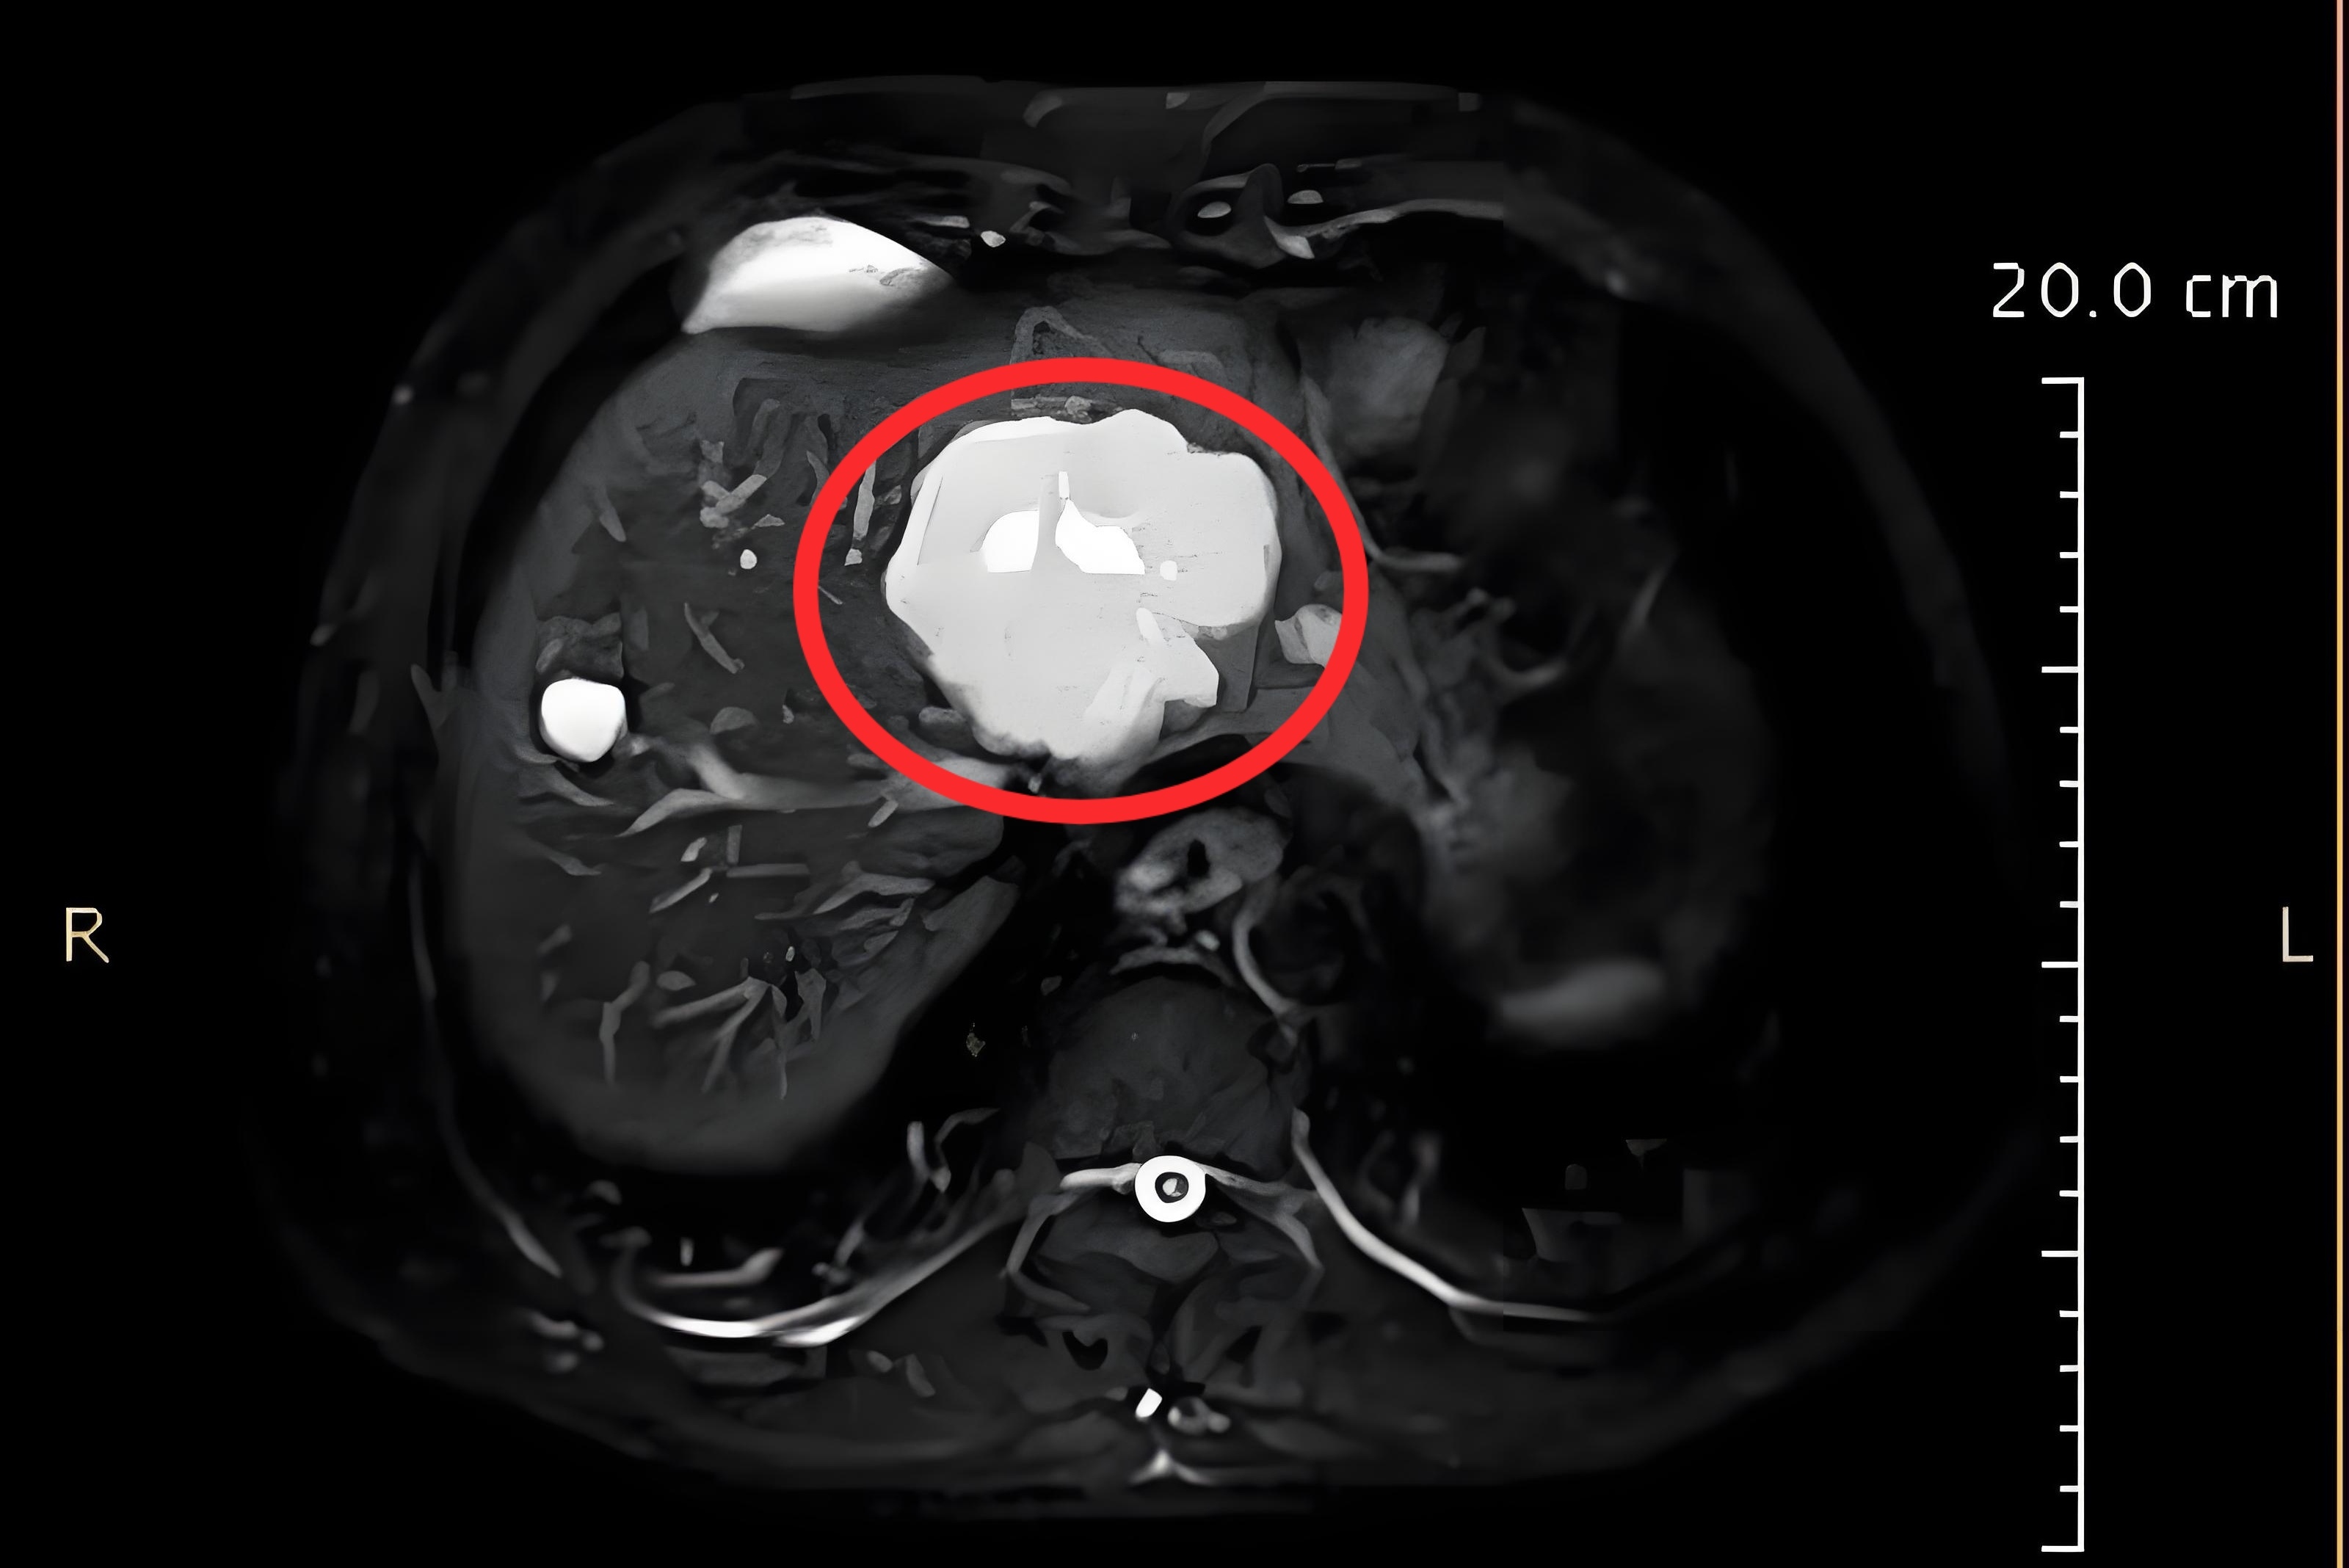

患者體檢查出來(lái)血管瘤很常見,部分患者很緊張,會(huì)糾結(jié)于報(bào)告中的每個(gè)字的描述。以下是一名腸癌患者,肝臟一枚典型血管瘤的CT和MRI表現(xiàn)。接下來(lái)是磁共振MRI表現(xiàn)

劉璐璐醫(yī)生的科普號(hào)2024年08月01日2473

引言隨著人們對(duì)健康的日益關(guān)注和定期體檢意識(shí)的提高,B超因其簡(jiǎn)單、無(wú)創(chuàng)的特點(diǎn)成為了腹部器官常規(guī)體檢的首選檢查手段。這導(dǎo)致越來(lái)越多的人被診斷出肝臟血管瘤。然而,許多人擔(dān)心這是否意味著他們患上了惡性腫瘤。本文將為您揭開肝臟血管瘤的真相。1.血管瘤是腫瘤嗎?血管瘤是一種由肝臟內(nèi)部血管組織異常增生所形成的良性腫瘤。雖然名稱中含有“瘤”,但它通常不會(huì)惡變。2.血管瘤會(huì)惡變嗎?不會(huì)。血管瘤是一種良性病變,不會(huì)轉(zhuǎn)變?yōu)閻盒阅[瘤。3.肝臟血管瘤的B超表現(xiàn)?典型特征:在B超上,血管瘤通常表現(xiàn)為高回聲區(qū),邊界清晰,邊緣規(guī)則。有時(shí)可以看到內(nèi)部或周邊的血流信號(hào)。?非典型表現(xiàn):盡管高回聲是血管瘤的典型表現(xiàn),但也有少數(shù)情況下血管瘤可能呈現(xiàn)為低回聲或混合回聲,這可能與肝臟其他惡性腫瘤如肝細(xì)胞癌的表現(xiàn)重疊。一個(gè)特殊的案例曾經(jīng)有一位40多歲的男性公務(wù)員,在20多年前通過(guò)B超檢查被診斷為肝臟血管瘤。在隨后的20年間,他定期復(fù)查,發(fā)現(xiàn)病灶在緩慢增大,最終甚至達(dá)到了20多厘米。最終,醫(yī)生建議他進(jìn)行磁共振成像(MRI)檢查,結(jié)果發(fā)現(xiàn)這不是血管瘤的典型表現(xiàn),建議手術(shù)切除,最終該患者確診為肝細(xì)胞癌。4.肝臟血管瘤的CT表現(xiàn)?CT平掃:血管瘤在CT平掃中通常表現(xiàn)為低密度灶、低密度結(jié)節(jié)或低密度腫塊,這一表現(xiàn)與肝臟其他惡性腫瘤如肝細(xì)胞癌相似。?CT增強(qiáng):在CT增強(qiáng)掃描中,血管瘤的強(qiáng)化方式通常描述為快進(jìn)慢出、持續(xù)強(qiáng)化、向心性強(qiáng)化或漸近性強(qiáng)化,但這些表現(xiàn)也可能與肝臟其他惡性腫瘤如肝內(nèi)膽管癌的表現(xiàn)重疊。5.肝臟血管瘤的MRI表現(xiàn)?T2加權(quán)像:在MRIT2加權(quán)像上,血管瘤通常呈明顯高信號(hào),像燈泡一樣亮,被稱為“燈泡征”。?擴(kuò)散加權(quán)成像(DWI)及ADC圖:在DWI及ADC圖上,血管瘤通常呈明顯高信號(hào)或描述為擴(kuò)散不受限。?增強(qiáng)掃描:增強(qiáng)掃描同樣顯示為快進(jìn)慢出、持續(xù)強(qiáng)化、向心性強(qiáng)化或漸近性強(qiáng)化。綜合各個(gè)序列表現(xiàn),基本能準(zhǔn)確診斷出血管瘤。6.是否需要使用肝臟特異性對(duì)比劑普美顯??結(jié)論:不需要。無(wú)論是血管瘤還是肝細(xì)胞癌,在使用普美顯增強(qiáng)掃描后均呈現(xiàn)為低信號(hào),因?yàn)檫@些病變都不是正常的肝細(xì)胞,因此使用普美顯對(duì)血管瘤的診斷沒(méi)有附加意義。7.血管瘤需要治療嗎??小病灶:對(duì)于直徑小于5厘米的血管瘤,通常建議定期復(fù)查為主。?大病灶或有癥狀:對(duì)于直徑大于5厘米的血管瘤或出現(xiàn)臨床癥狀的血管瘤,可以考慮手術(shù)或影像引導(dǎo)下的介入治療。8.結(jié)論如果您被診斷為肝臟血管瘤,請(qǐng)不要過(guò)度擔(dān)憂。大多數(shù)情況下,定期復(fù)查就足夠了。當(dāng)懷疑是血管瘤時(shí),可以行MRI增強(qiáng)掃描輔助診斷。了解血管瘤的真實(shí)面貌,有助于我們更加理性地面對(duì)這一情況。。